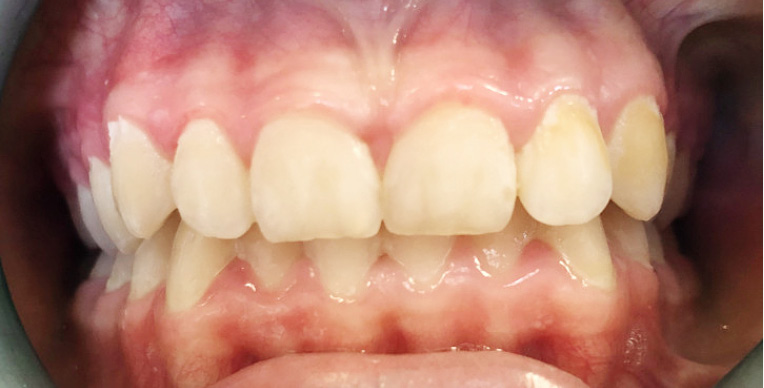

STRESZCZENIE: Praca przedstawia opis przypadków pacjentów, u których stwierdzono zmiany hipomineralizacyjne szkliwa zębów przednich, leczonych preparatem ICON DMG®. Metoda infiltracji jest jedną z nieinwazyjnych metod leczenia. Na podstawie opisanych przypadków przedstawiono efekty i skuteczność leczenia. Jej zastosowanie pozwala na uzyskanie zadowalającego efektu, w pełni akceptowalnego przez pacjentów. Procedura jest nieskomplikowana dla operatora i nie powoduje skutków ubocznych.

SUMMARY: The paper presents the case reports of patients with hypomineral changes in the front tooth enamel which were treated with the ICON DMG® preparation. The current dentistry offers a possibility of a non-invasive treatment for enamel changes. In this paper, the causes and classification of enamel disorders are discussed based on selected literature. The results and effectiveness of the therapy with ICON DMG® are presented based on our own research. The treatment demonstrates promising results. It is easy to carry out, well tolerated by patients and causes no side effects.